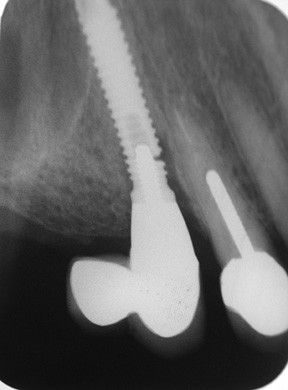

Рентгенография. Позволяет отличить периимплантный мукозит от периимплантита: при мукозите на рентгенограмме нет патологических изменений вокруг имплантата; при периимплантите видно убыль кости. Также рентген помогает определить глубину зондирования и увидеть плохое прилегание элементов протеза [14] .

![Периимплантит на рентгенограмме [18]](/pimg3/mukozit-prichini-simptomi-1A72CC.jpeg)